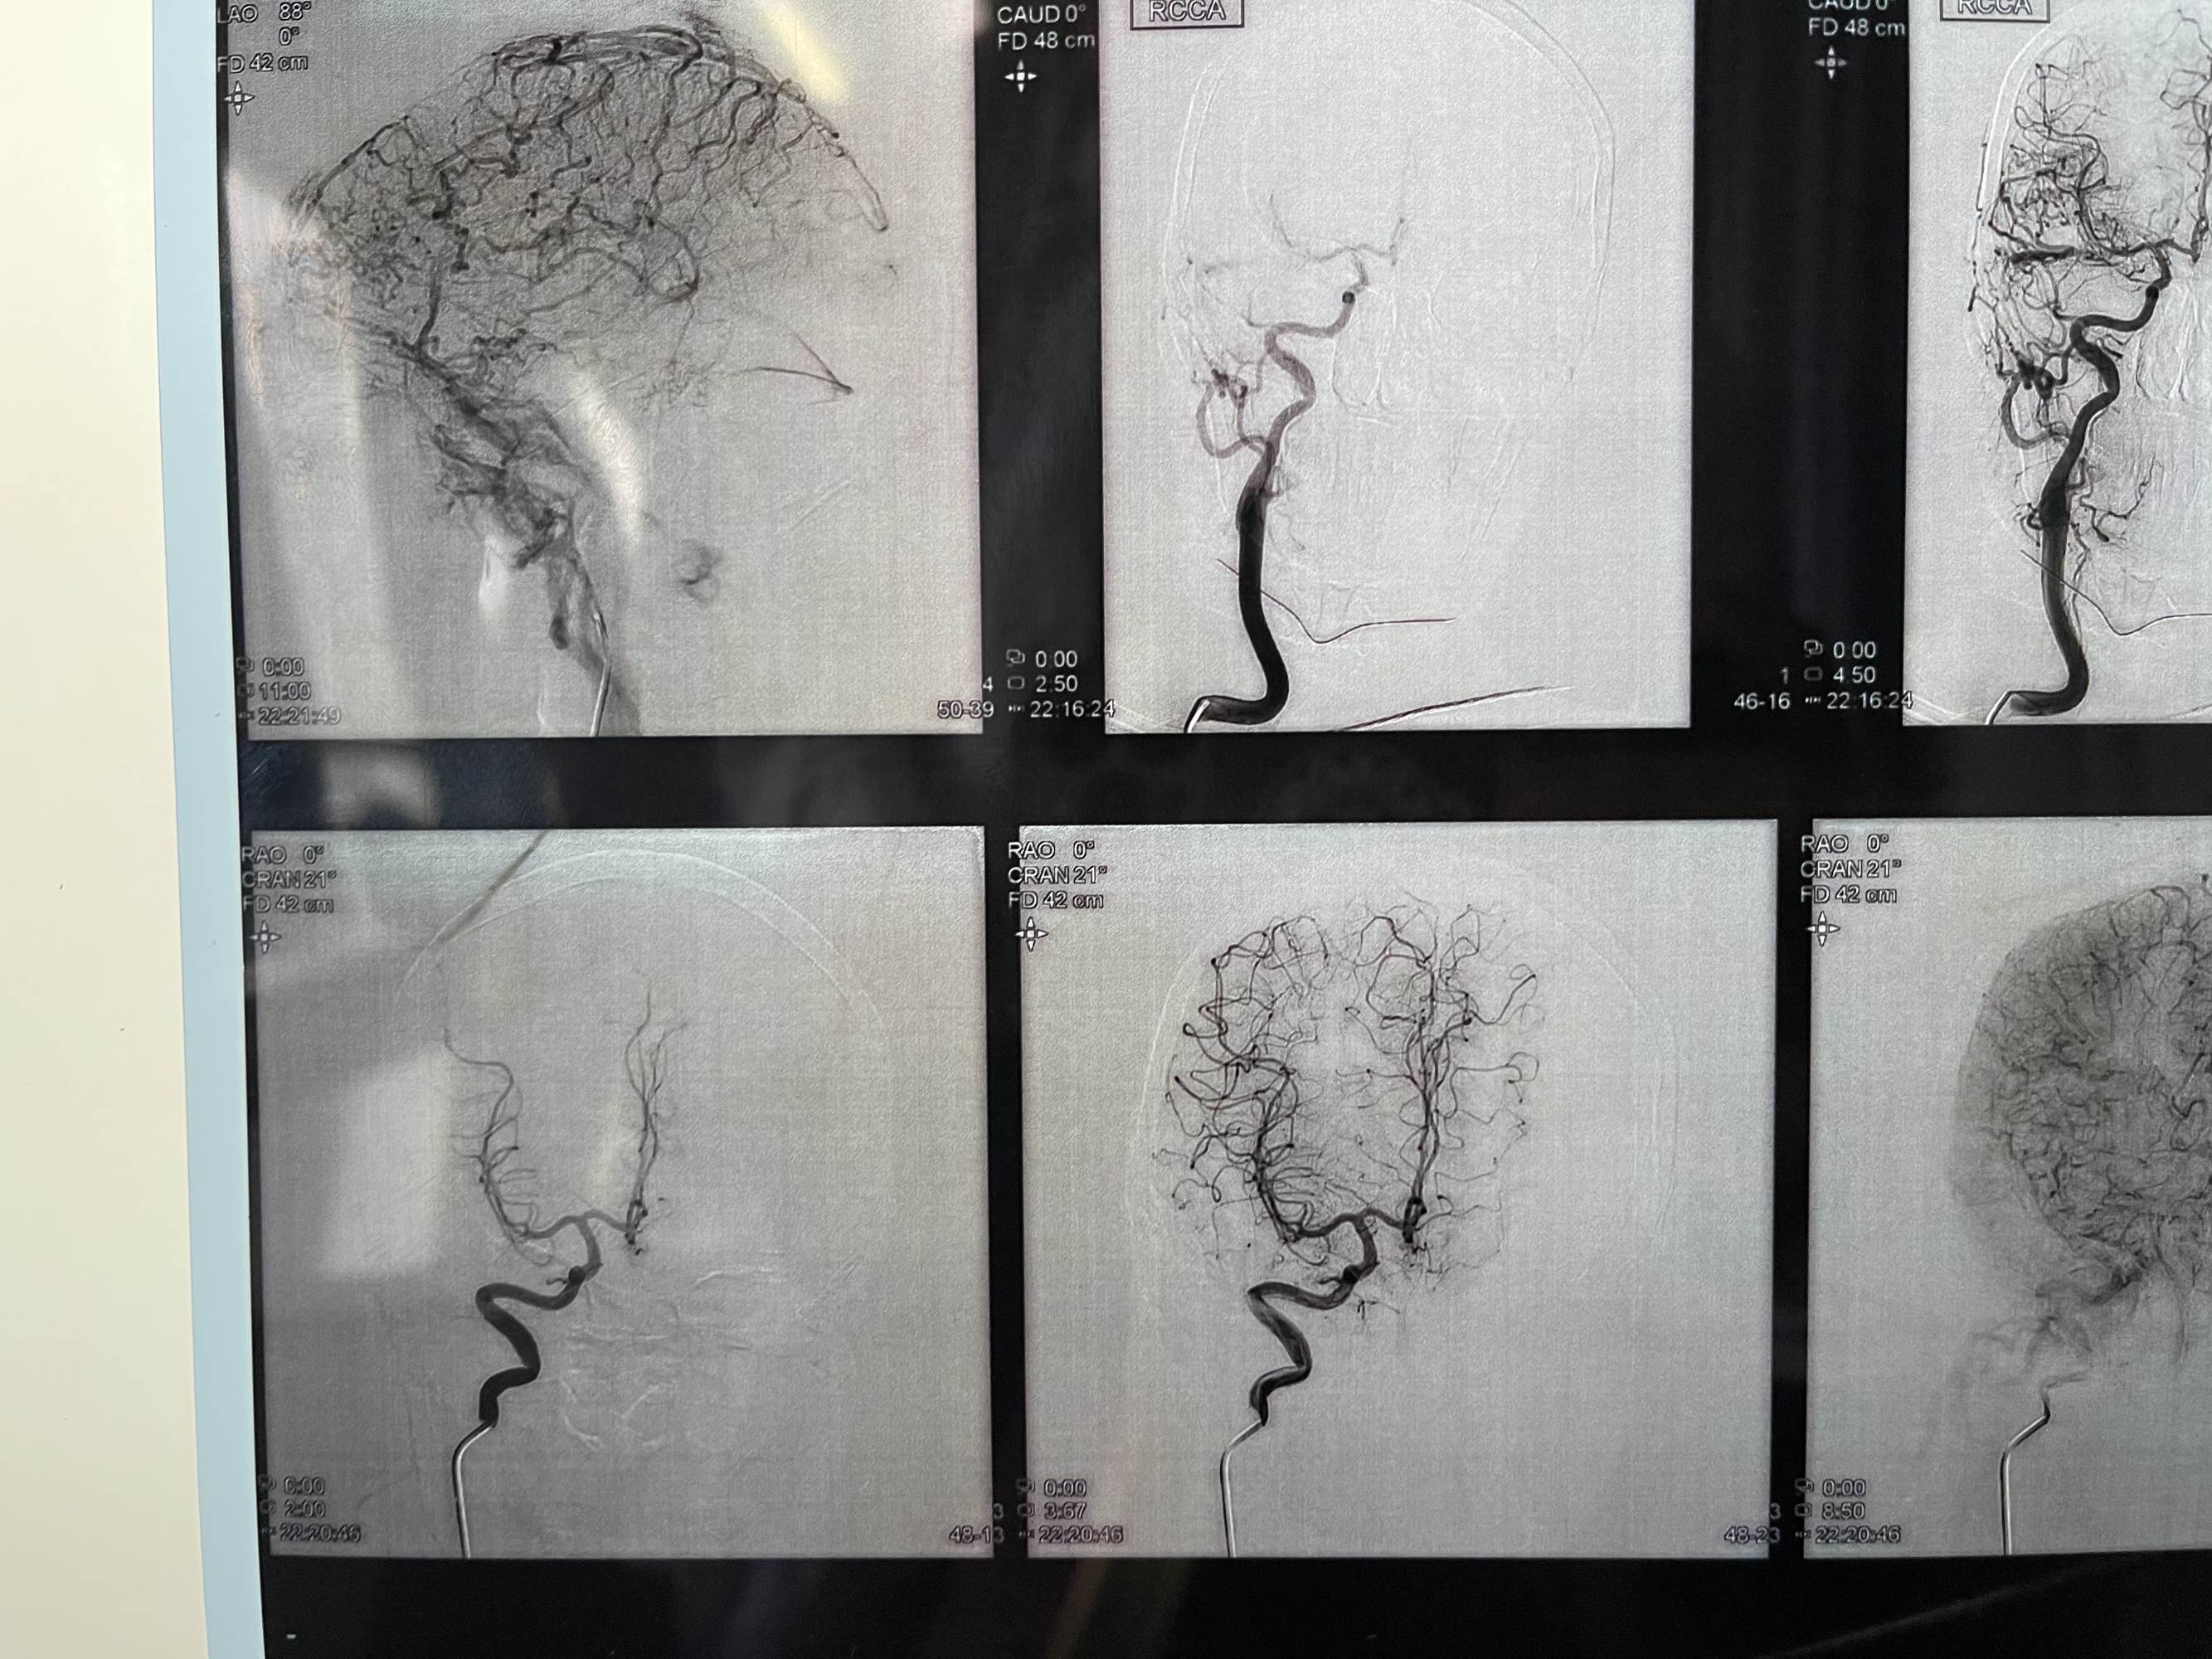

患者女性,68岁,头痛入院,行造影检查硬脑膜动静脉瘘,双侧脑膜中及枕动脉主要供血,开口位于枕部,皮层引流静脉代偿性粗大,拟介入栓塞

看看术前造影,迂曲的静脉,上矢状窦后三分之一及横窦已经不显影了

微导管到达瘘口,打胶

患者女性,68岁,头痛入院,行造影检查硬脑膜动静脉瘘,双侧脑膜中及枕动脉主要供血,开口位于枕部,皮层引流静脉代偿性粗大,拟介入栓塞

看看术前造影,迂曲的静脉,上矢状窦后三分之一及横窦已经不显影了

微导管到达瘘口,打胶